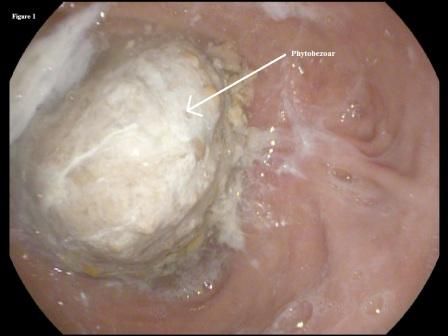

She followed this regimen for the following 3 months with significant improvement in her symptoms. A repeated upper endoscopy performed at 3 months after presentation showed complete dissolution of the phytobezoar, with a clear view of the distal end of the gastric remnant (Figure 3) and the jejunal side of the anastomosis (Figure 4).